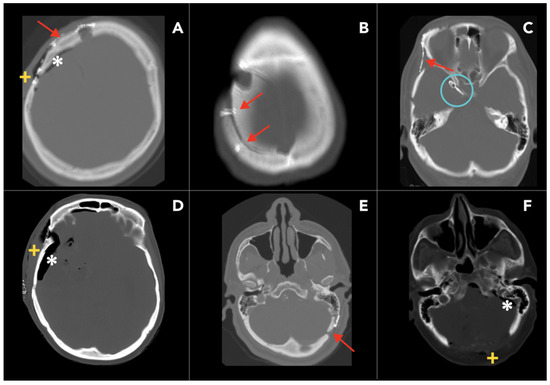

2.1.1. Craniotomy